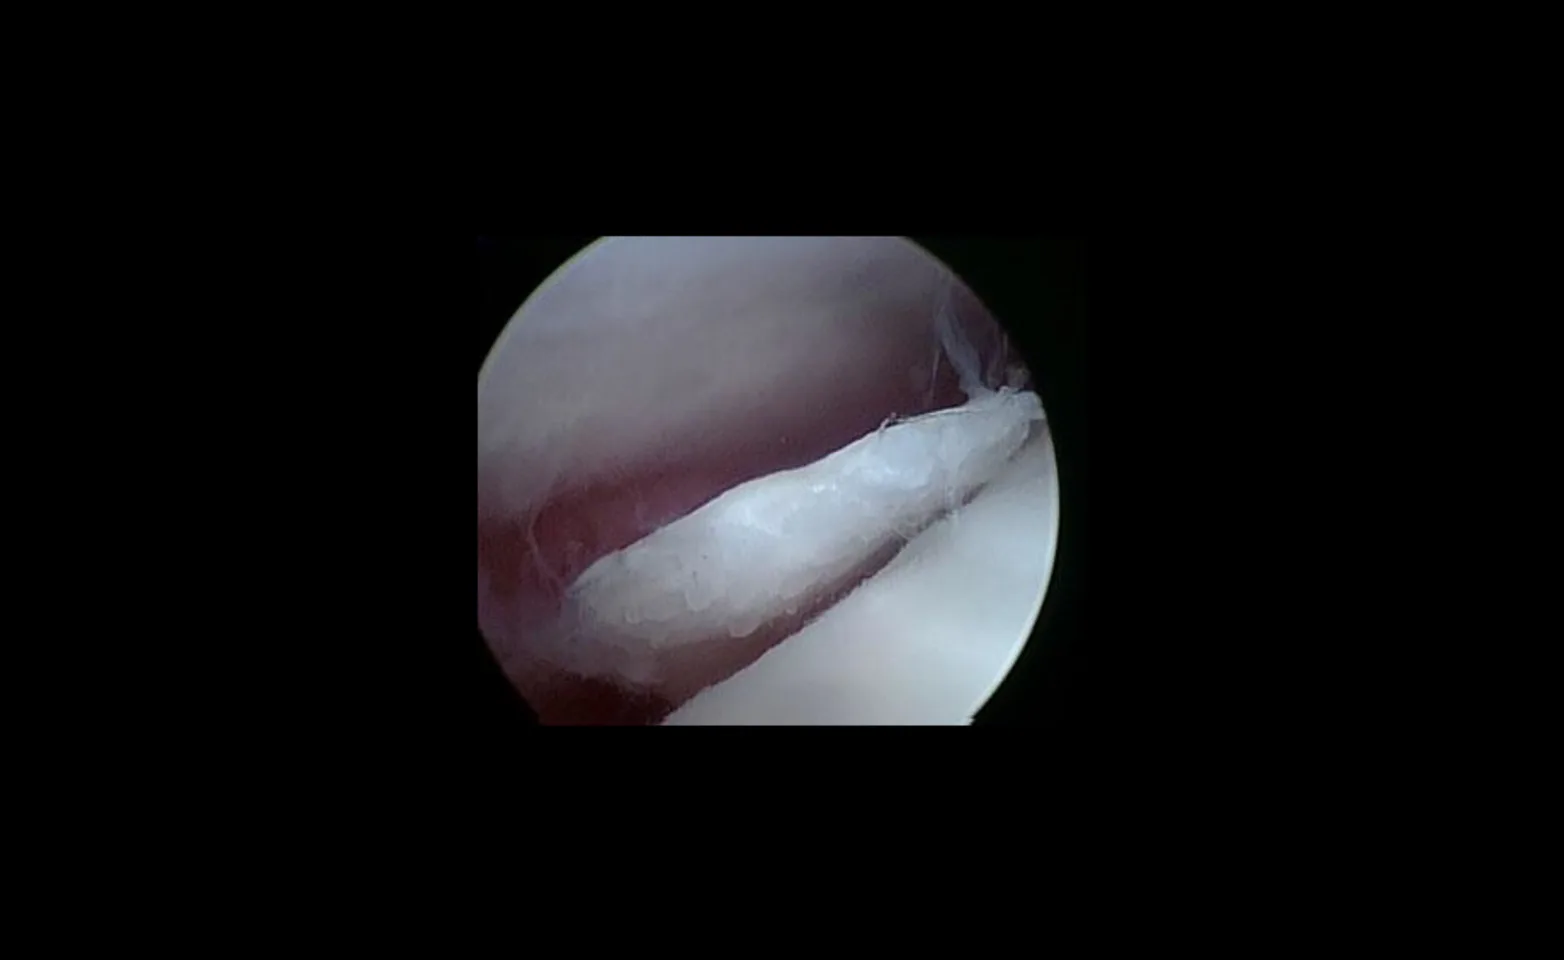

Arthroscopic view of a large cartilage ap in the shoulder of a dog, called caudal humeral osteochondritis dessicans.